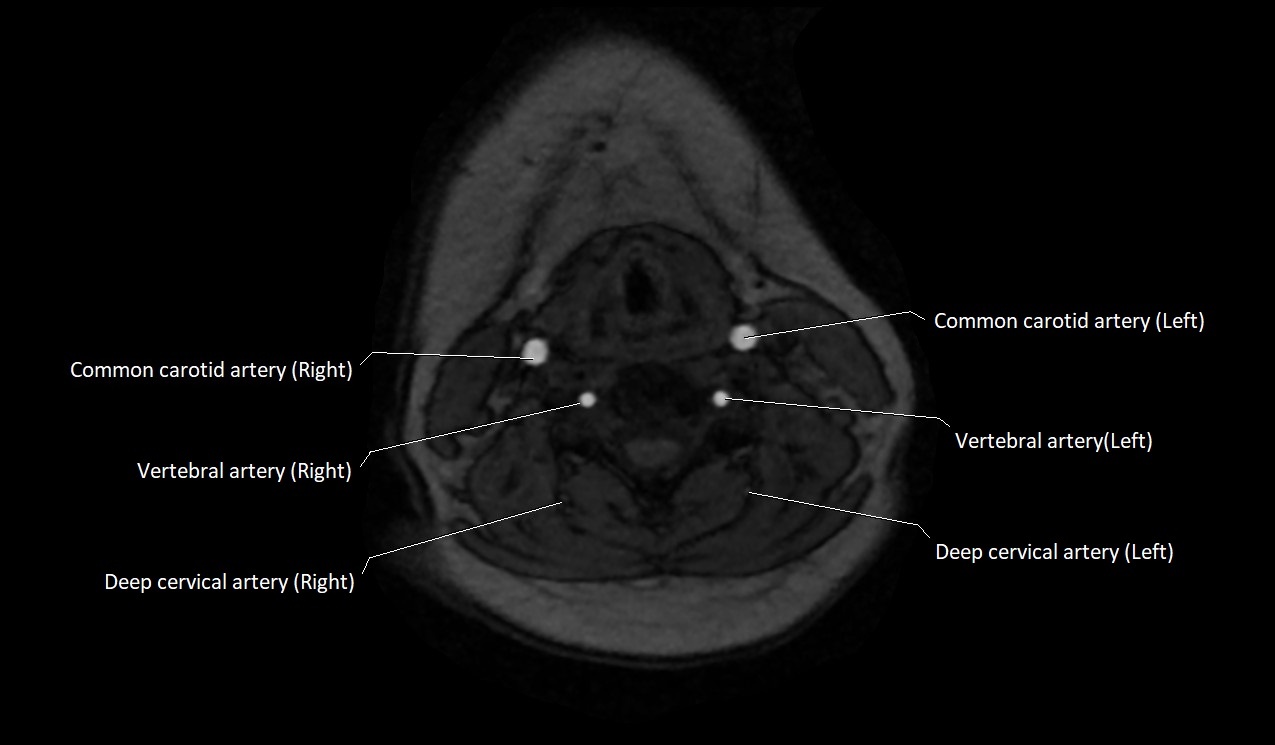

MRI images

image